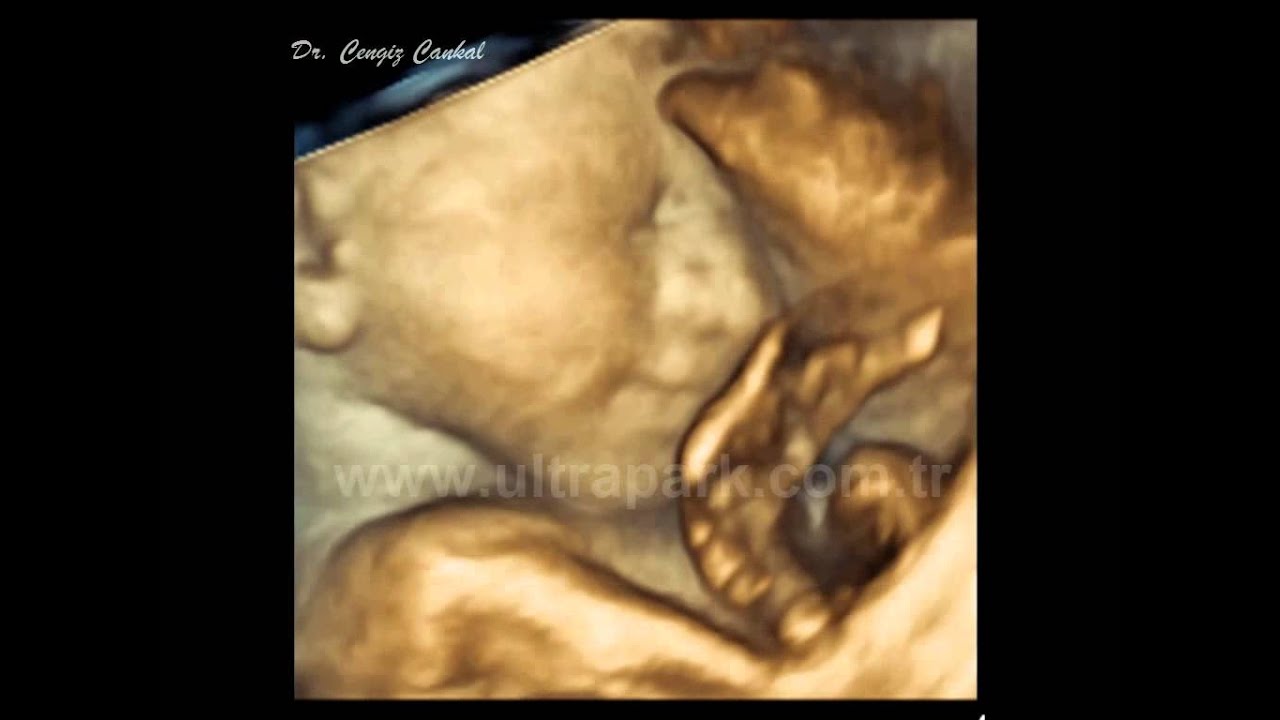

28+4 haftalık (6.5 aylık) gebelikte ultrasonda anne karnında bebek

Bebekler aslında 7 haftalıktan itibaren hareket etmeye başlarlar. Haftasında, ultrason muayenesine girdiğinde bebeğinin kalp atışlarını ilk kez. Bebeğin ters durması, anne karnında bebeğin kafası yukarıda popusu aşağıda olarak durması olarak adlandırılır.